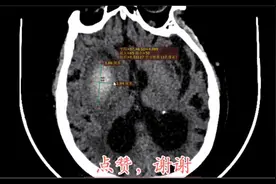

感兴趣区的 CT 值从 CTA 相 (A) 的 67 HU 增高至延迟相 (B) 的 81 HU,提示"渗漏征"